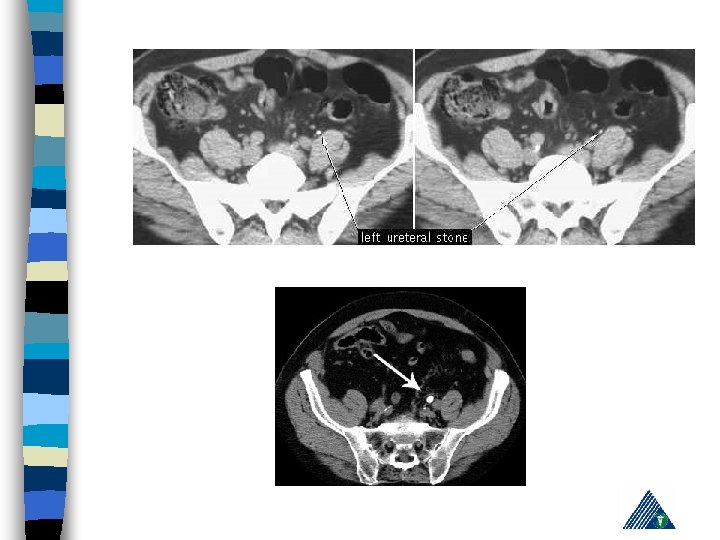

R: Appendicitis - Cholelithiasis n urinalysis: hematuria n KUB n IVP n Computerized Tomography n Pain management, hydration, hot bath n Treatment of the underlying cause n

Radiologic Imaging n n n KUB (loss of psoas or renal contour) IVU (delayed renal function, nonhomogenous collecting system) USG (lumbar hematoma and urinoma lokalizasyonu) Computerized Tomography Renal angiography